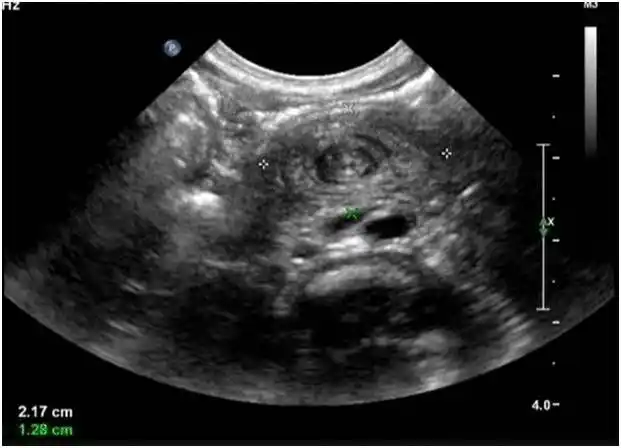

「漩涡征」:超声诊断小肠扭转的线索